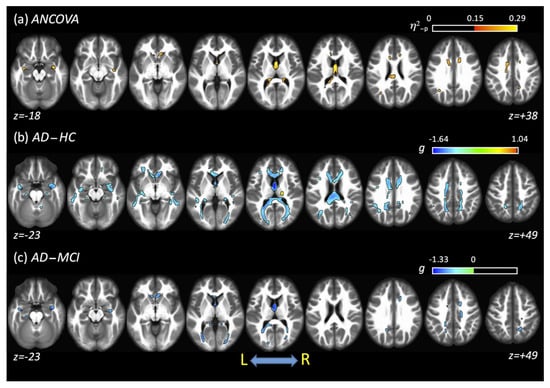

3.2. ANCOVA Results: FSL–LLS

3.5. Post Hoc: AD versus HC

3.6. Post Hoc: AD versus MCI

3.7. Post Hoc: MCI versus HC